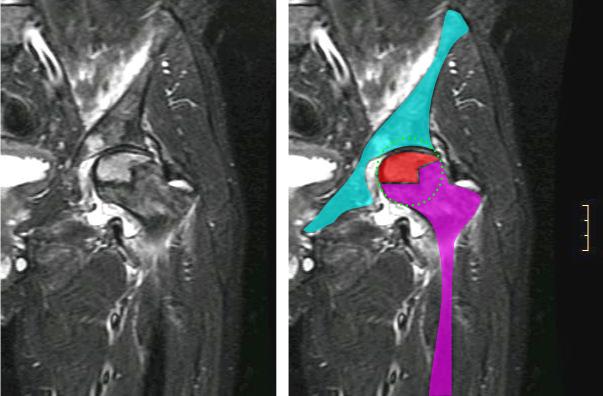

Giant Cell Tumor of the Bone

Giant cell tumor of the bone is composed of multinucleated giant cells and stromal cells that occur in young adults.

Giant cell tumor of the bone typically arises in the epiphysis of long bones, usually the distal femur or proximal tibia.

Radiology of giant cell tumor of the bone classically shows a “soap-bubble” appearance on x-ray.

Giant cell tumors of the bone are locally aggressive, and they may recur after surgical removal.